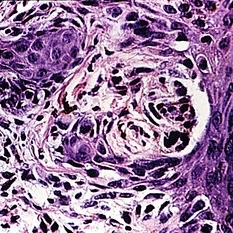

Slide 5-43 Slide 5-43Feb 25 2019 by Lancaster Course in Ophthalmology Nest of atypical melanocytes resembling a junctional nevus at the edge of a superficial spreading melanoma in a 70-year-old female. Note the inflammatory cells in the dermis. Condition/keywords: junctional nevus, melanocytes, melanoma